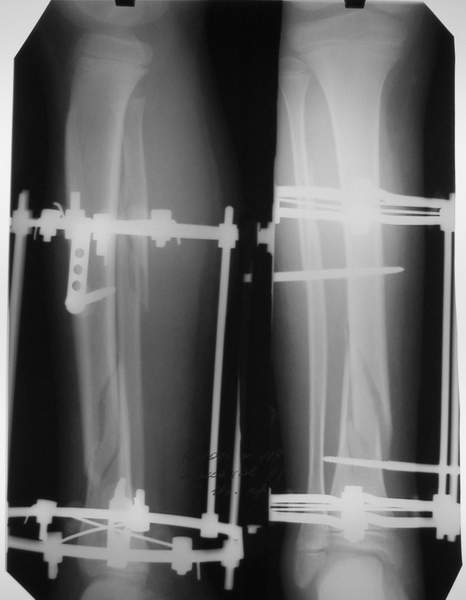

3a

3b

3c

В аттачте № 3 - один из примеров полукольцевого аппарат...

Это уже я баловался.

Итог? Работы больше (по времени и

интраоп "подгонке"), срастается также, а особого преимущества по сравнению с

"чиста" кольцевым (вес, удобство ношения и пр.) - я, по крайней мере,

не нашел.

Теперь не балуюсь.

Может быть зря?